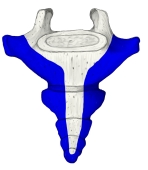

尾 骨 ( びこつ、英:coccyx )

尾骨とは 「日本人体解剖学 (上巻) 「 胎児期には9個の尾椎の原基が存在するが、胎児の成長と共に下方のものから次第に退化し、結局上方の3~5個の尾椎だけが残り融合してできた骨で、尾椎の数には個人差がある。」 また、「Wikipedia」には以下のような解説が見られる。 「Most anatomy books incorrectly state that the coccyx is normally fused in adults. In fact it has been shown that the coccyx may consist of up to five separate bony segments(区分), the most common configuration(形状) being two or three segments.」

・全体としては逆三角形の形を呈する。

・第1尾椎にあたる部分の下から第1尾椎神経が出るが、それ以下からは神経は出ない。 ・仙骨と骨化(ossification)しない場合は、椎間円板を介して関節する。(仙尾関節)